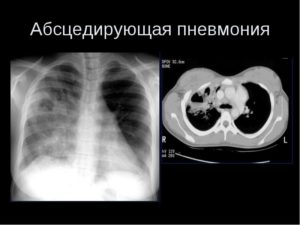

Обследование в обязательном порядке включает обзорную рентгенограмму легкого. На ранней стадии абсцедирующая пневмония схожа с другими заболеваниями дыхательной системы, и грамотно проведенная рентгенограмма позволит точно определить характер патологии. Рентгенограмма показывает, насколько распространен патологический процесс, его локализацию, возникновение дополнительных осложнений.

При затруднении в постановке точного диагноза и определении степени распространения патогенного процесса поможет компьютерная томография. Исследование позволяет четко визуализировать поражения легкого, возникшие при заболевании.